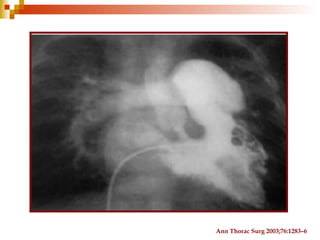

Cateterismo cardiaco

Ann Thorac Surg 2003;76:1283–6